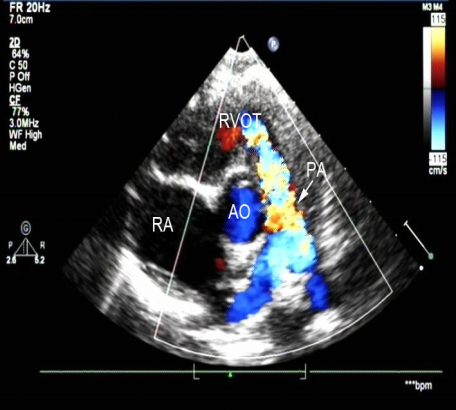

法洛四联症:超声心动图表现

室间隔缺损、主动脉骑跨

右室流出道狭窄